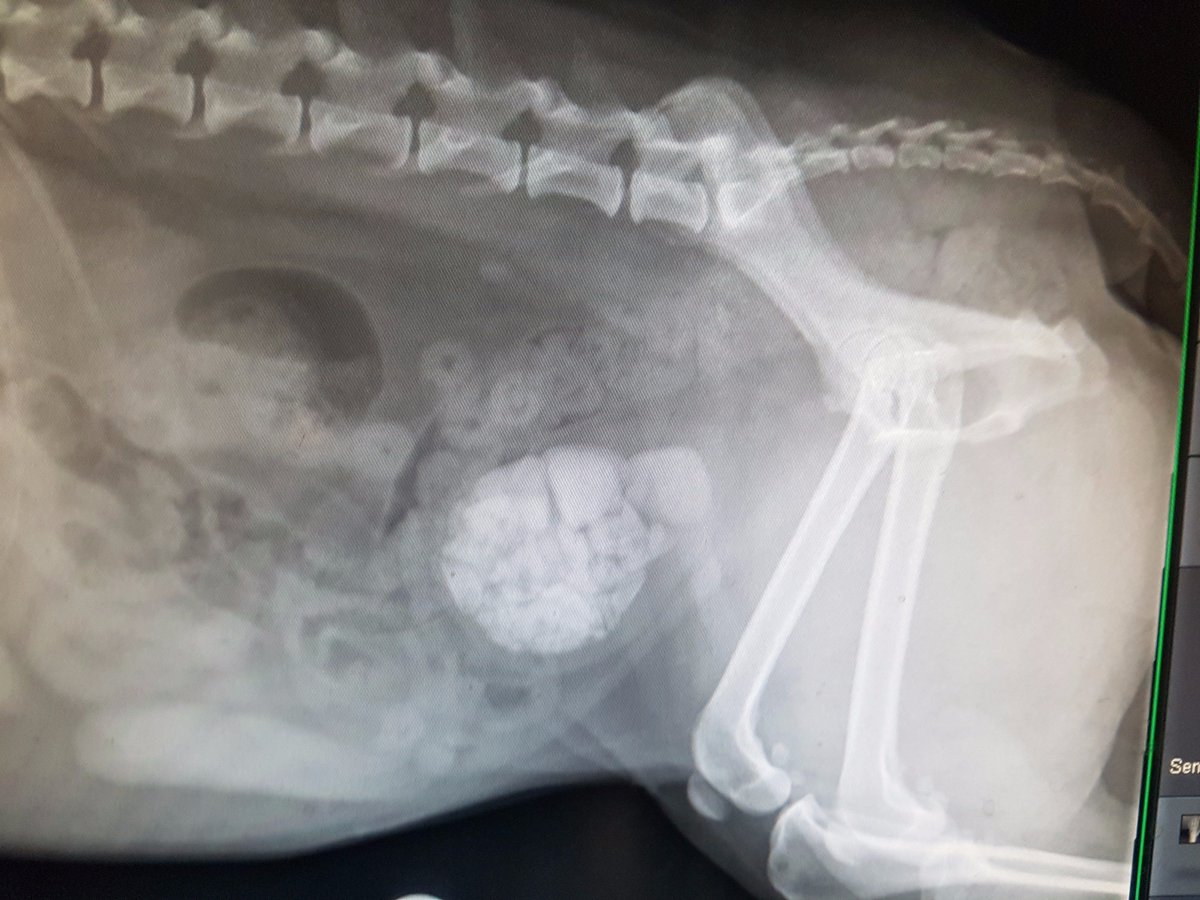

We removed 139 stones from Pepsi's bladder during her cystotomy!! She is doing much better now! :) #dogsoftwitter twitter.com/VetsKlinic/sta…

How many stones did we removed from Pepsi during her cystotomy? Can you guess? Pepsi is recovering well #vets #dogsoftwitter